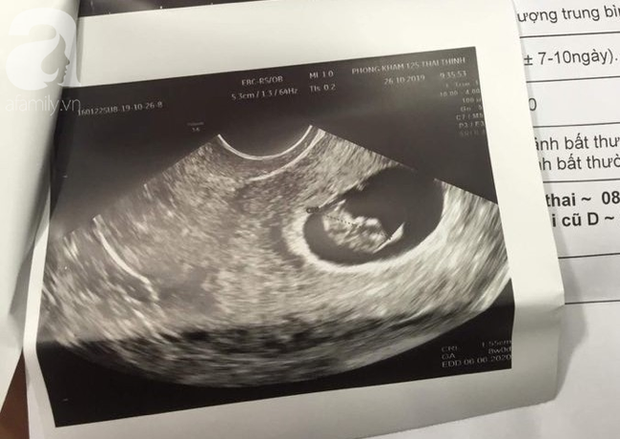

Kết quả siêu âm của chị A. tại một BV ở Hà Nội.

Đến ngày 29/10 vì lo sợ, chị A. được gia đình đưa đến một BV tại Hà Nội điều trị. Kết quả xét nghiệm tại đây khiến mọi người ngỡ ngàng khi nữ bệnh nhân được phát hiện đang mang thai 8 tuần. Như vậy vào thời điểm thực hiện hút mỡ bụng, cái thai trong bụng chị A. đã 4 tuần tuổi.

Bác sĩ cũng cho biết chị A. không thể giữ thai vì có thể gây nguy hiểm tính mạng cho mẹ và bé.

Kết quả chẩn đoán có thai tiếp tục được khẳng định tại BV AIH (TP.HCM).

Sau đó, gia đình tiếp tục đưa chị A. đến xét nghiệm, siêu âm tại Bệnh viện AIH (TP.HCM). Kết quả vẫn chẩn đoán người phụ nữ có thai.